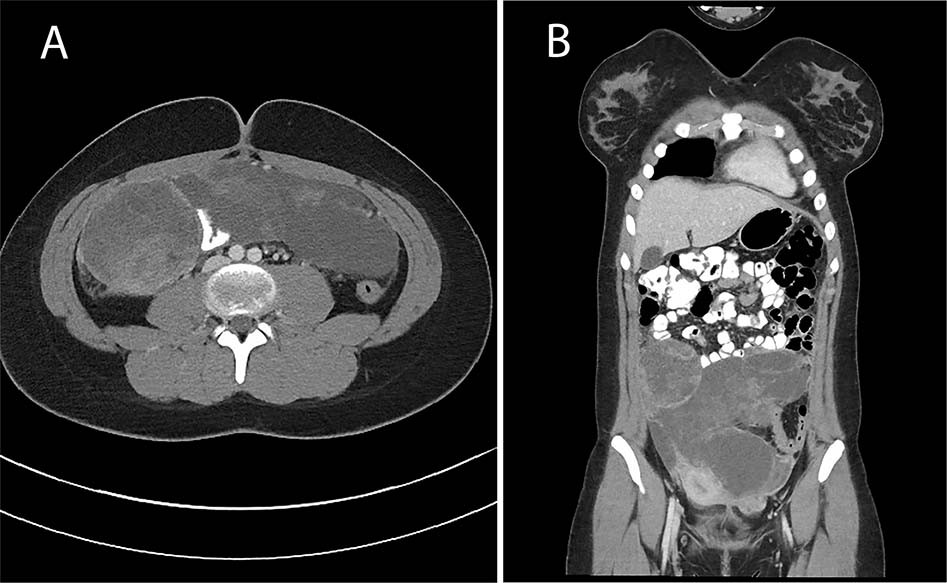

Fig. 3: Case 4.

Axial (a) and coronal (b) computed tomography images demonstrate a heterogeneous low attenuation lobulated intraperitoneal mass with nonenhancing regions suggesting intratumoral necrosis extending from the level of the umbilicus to the lower pelvis, similar in appearance to a type III PPB.